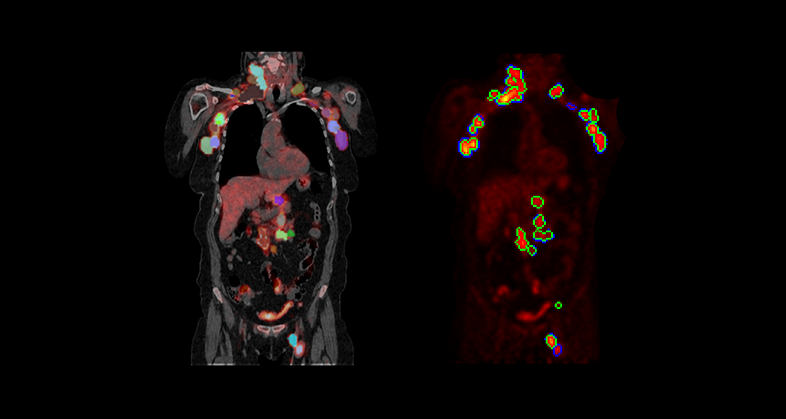

Prognostic value of genetic alterations and 18F-FDG PET/CT imaging features in diffuse large B cell lymphoma

Predicting survival, neurotoxicity, and response in B-Cell lymphoma patients treated with CAR-T therapy using an imaging features-based model